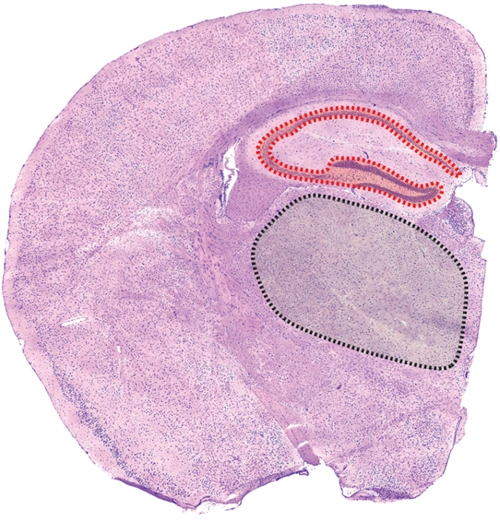

小鼠脑组织海马体染色切片问题~ 求解

鼠脑he染色石蜡切片